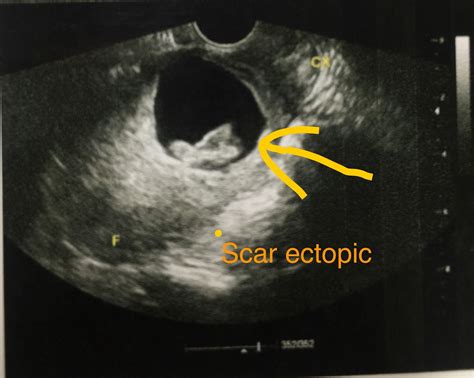

• Tubal Surgery or Damage: Previous surgeries on the fallopian tubes or conditions like pelvic inflammatory disease (PID) can cause scarring that prevents the egg from reaching the uterus.

• types of ectopic pregnancy ultrasound

• ultrasound picture of ectopic pregnancy